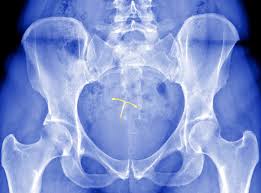

Https Obgynpc Com Wp Content Uploads 2019 11 Iud Post Insertion Instruction Sheet 2019 Pdf from However, not being able to feel the strings. Yes, you may experience some spotting after an iud removal, but as long as it isn't heavy and goes away in a few hours or, at worst, a couple of days, that's totally normal, the mayo clinic. As long as you don't feel the plastic of the iud sticking out of your cervix you're good! But you can expect more bleeding than before — at least for a while. Me again, with another question. The copper iud might increase your period pain and bleeding or cause bleeding between periods, the acog says. If this happens, talk to your doctor as they will have to put it back in place. Ive had my copper iud for about 18months so i know how the strings should feel, i also take the pill as i have period issues (joy) im at the end of my pill pack (last pill today) but have been spotting the past few days (this might be nothing as i suffer bleeding issues) today i decided to check the strings anyway and it doesn't feel right i can barely feel anything but a small spikey end of.

It helps to know what the strings feel like before you try to find them, so don't feel too shy to ask if you can touch them before your iud. The patient may specifically voice a concern that the iud is out of place, either because of symptoms such as pain or bleeding or because she can no longer feel the iud strings. That's why it's not recommended for people with conditions like endometriosis that can. This bleeding can be annoying at first but usually will become lighter with the mirena iud quickly. If you think your iud is out of place, call your health care provider asap and ask for an appointment. Month5 for mirena (levonorgestrel) iud. Gupta notes, the strings of the iud are thin and soft enough that they should not be sensed during intercourse. You have unexplained vaginal bleeding; You definitely want to talk to them if you have severe pain, cannot find your strings, notice the strings are shorter or longer than normal, or can feel the iud poking out. The copper iud might increase your period pain and bleeding or cause bleeding between periods, the acog says. They will usually feel like thin bits of fishing line. If the iud strings feel longer or shorter compared to the last time you checked them, or if you could feel the plastic of your iud, then it could mean that your iud has moved. Can feel the strings poking me inside, and its uncomfortable and annoying.